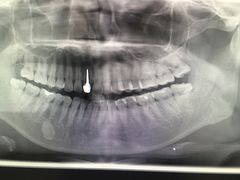

• 固瑞齿科(国贸门诊店)

• -固瑞齿科(国贸门诊店)